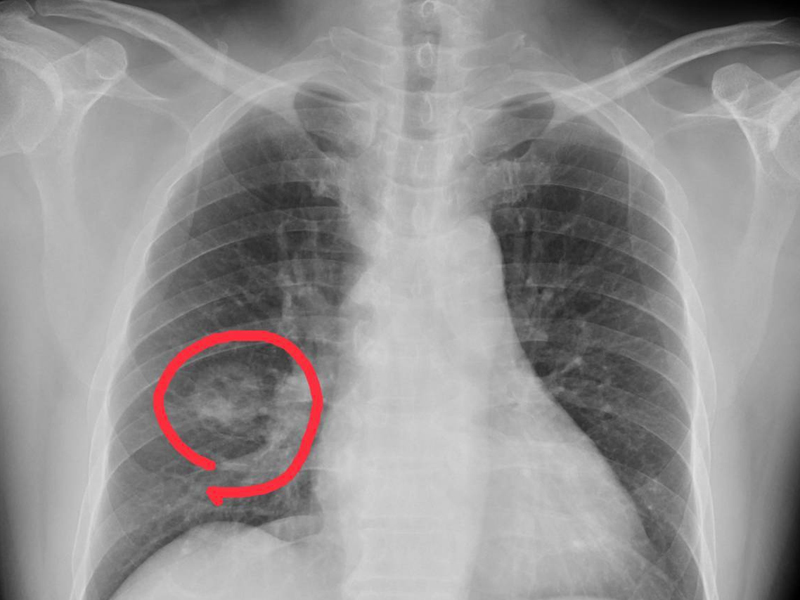

2. 腿部栓塞

引起腿部栓塞的原因有很多,血栓是比較常見的一種,癌症也是其中一種。當下肢出現不明原因的栓塞,要警惕是宮頸癌、肺癌、乳腺癌的可能。